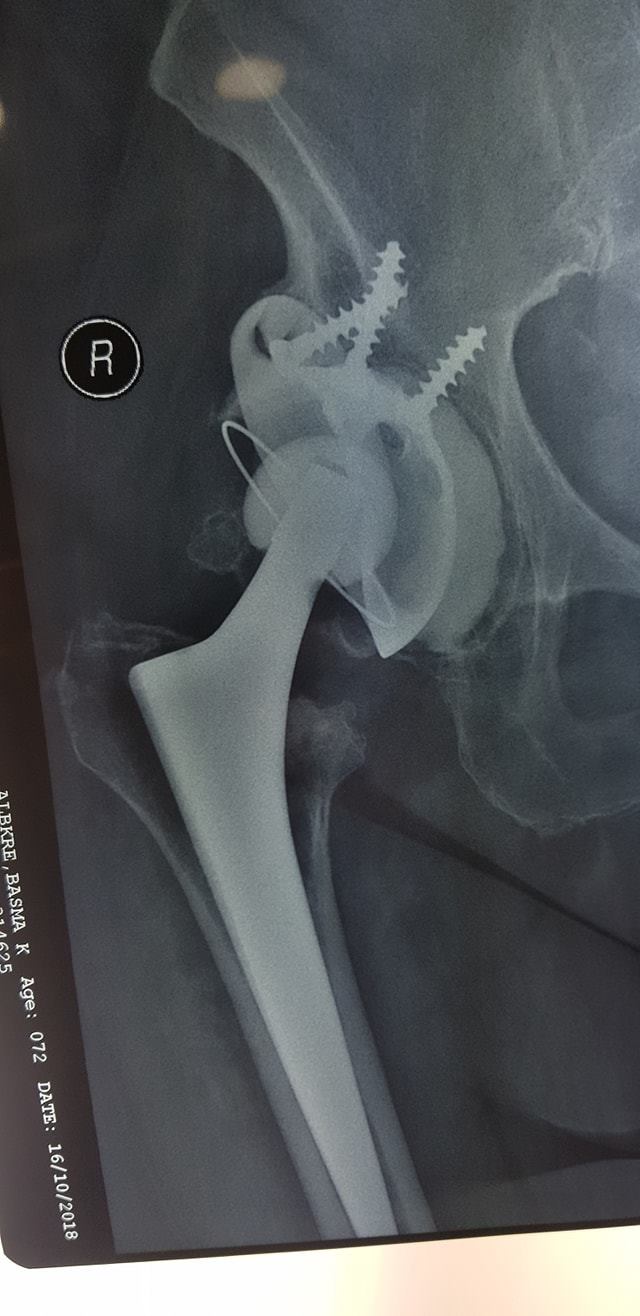

زراعة المفاصل الصناعية ورك و